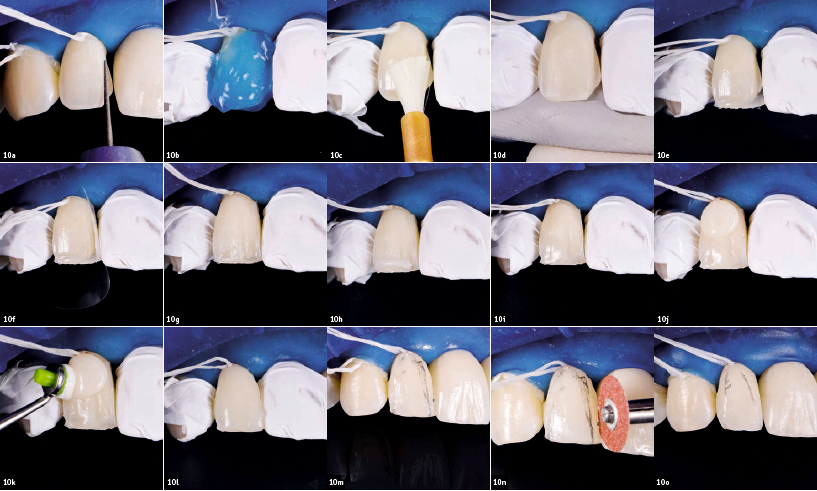

Με τις προσωρινές στεφάνες και το ομοίωμα ρητίνης των πλαγίων τομέων, θα μπορούσε να μεταφερθεί η μορφολογία του κερώματος. Αυτό το πρότυπο χρησιμοποιήθηκε για την αξιολόγηση του νέου χαμόγελου ενδοστοματικά πριν την κατασκευή των μόνιμων αποκαταστάσεων. Πραγματοποιήθηκε χρωματοληψία με τη βοήθεια διασταυρούμενου πολωμένου φωτός. Οι ανεπιθύμητες αντανακλάσεις εξαλείφθηκαν αποτελεσματικά με ένα ειδικό φίλτρο για τα μάτια. Για να κατασκευαστούν οι μόνιμες προσθετικές αποκαταστάσεις, ντουμπλαρίστηκαν οι προσωρινές και δημιουργήθηκαν αντίγραφα 1:1 με IPS e.max Press(μονολιθικό διπυριτιούχο λίθιο, Ivoclar Vivadent). Κοχλιούμενες στεφάνες από IPS e.max Press τοποθετήθηκαν στα εμφυτεύματα και οι οπές πρόσβασης των βιδών εμφράχθηκαν με PTFE και καλύφθηκαν με ρητίνη. Μόλις τοποθετήθηκαν οι αποκαταστάσεις, οι πλάγιοι τομείς κτίστηκαν με ρητίνη IPS Empress Direct (Ivoclar Vivadent).

Χρησιμοποιήθηκε ένα υπερώιο κλειδί σιλικόνης ως βοήθημα. Ο χρωματικός συνδυασμός της επιλεχθείσας ρητίνης και του κεραμικού υλικού IPS e.max φαινόταν ιδανικός. Χρησιμοποιήθηκε ελαστικός απομονωτήρας για απομόνωση. Εφαρμόστηκε μία τεχνική διαστρωμάτωσης ρητίνης για να κτιστούν οι τομείς (εικ. 10A-s). Η αδαμαντίνη αδροποιήθηκε ελαφρώς (37% φωσφορικό οξύ, 15”, ολική αδροποίηση) και στη συνέχεια επικαλύφθηκε με φωτοπολυμεριζόμενο συγκολλητικό παράγοντα. Το συγκολλητικό επαλείφθηκε στην επιφάνεια συγκόλλησης και στη συνέχεια φωτοπολυμερίστηκε. Αρχικά, κτίστηκε το υπερώιο κέλυφος αδαμαντίνης με IPS Empress Direct Enamel A2 και δημιουργήθηκε ένα υπερώιο κλειδί σιλικόνης από το ομοίωμα. Χρησιμοποιήθηκε χρώμα οδοντίνης Α3 για το κυρίως σώμα της οδοντίνης και τα ιδιαίτερα ανατομικά χαρακτηριστικά.

Επετεύχθη ένα αποτέλεσμα φυσικής εμφάνισης λόγω της ημιδιαφάνειας των κοπτικών άκρων με ρητίνη IPS Empress Direct TransOpal. Στη συνέχεια, η ανασύσταση καλύφθηκε με ένα στρώμα ρητίνης IPS Empress Direct Enamel A2. Η μορφολογική δομή διαμορφώθηκε και τονίστηκε με λεπτόκοκκες φρέζες διαμαντιού, φρέζες Arkansas, και ελαστικά στίλβωσης. Χρησιμοποιήθηκαν σιλικονούχες φρέζες στίλβωσης και πάστα διαμαντιού για την τελική στίλβωση. Το αποτέλεσμα ήταν μία αρμονική εμφάνιση των άνω προσθίων δοντιών όσον αφορά το σχήμα, το χρώμα και το μέγεθος (εικ. 11a&b).